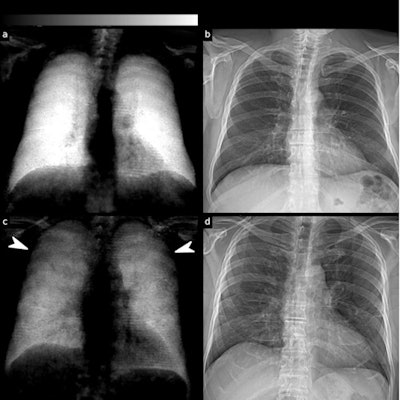

(a) Dark-field and (b) conventional (attenuation-based) chest radiographs of a healthy subject. The dark-field radiograph exhibits a strong, homogeneous dark-field signal. The respective attenuation-based image shows no apparent pathology. (c) Dark-field and (d) attenuation-based chest radiographs of a patient infected with COVID-19. Compared with the healthy subject, the infected patient shows an overall decrease of signal intensity. While the signal of the healthy subject is homogeneous, the dark-field signal of the infected patient appears inhomogeneous and patchy, especially in the periphery of the lung (arrowheads). Image courtesy of Research Square.In a receiver operating characteristic (ROC) analysis for the differentiation between infected patients and healthy subjects, the effect size expressed as area under the ROC curve (AUC) was 0.78 for standard radiographs, 0.91 for dark-field images, and 0.93 for the combination of both.